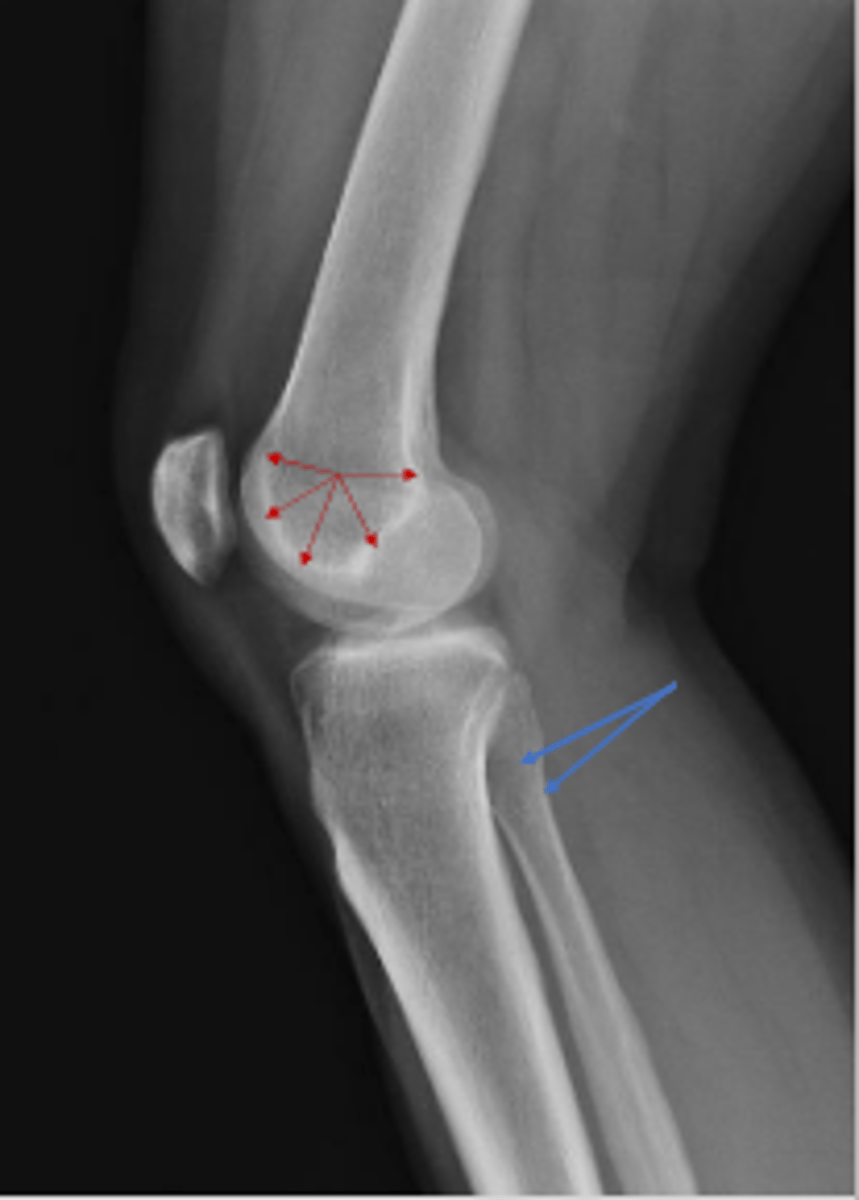

What are the blue arrows pointing to?

Ludloff's space/triangle

What are the red arrows pointing to?